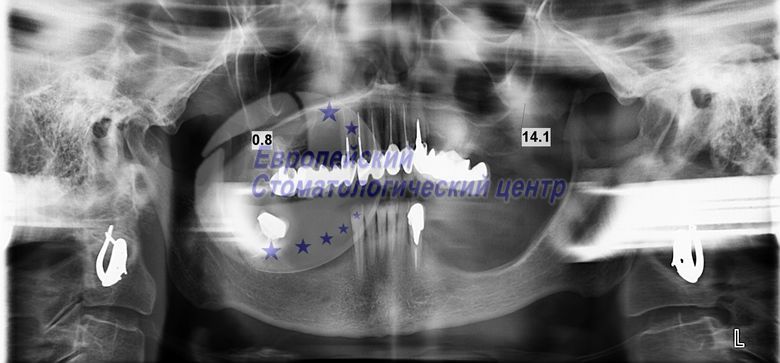

В данной клинической ситуации перед хирургическим вмешательством имелись периодонтитные (воспаление тканей, окружающих корень зуба) зубы на верхней и нижней челюсти, которые подлежали удалению. Так же имелся дефицит костной ткани на верхней и нижней челюсти. Для того, чтобы установить имплантаты по классической методике необходимо провести много операций по восстановлению костной ткани на верхней и на нижней челюсти. Мы согласовали оперативное вмешательство без дополнительных вмешательств в кратчайшие сроки. С немедленной установкой имплантатов и немедленной нагрузкой. На нижней челюсти установлены имплантаты в обход нижнечелюстного канала. А на верхней челюсти установлены имплантаты в обход синуса гайморовой пазухи верхней челюсти в бугор верхней челюсти. Пациент получил быструю реабилитацию без осложнений. Временные коронки получил через три дня после операции. Постоянные коронки из биологически инертного материала РЕЕК через четыре месяца.

опг через год после операции